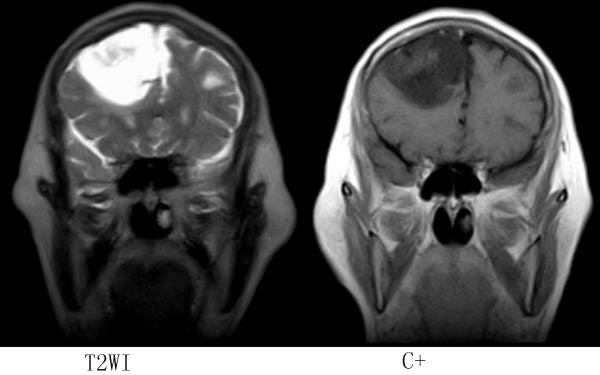

女,64岁,ct示右侧额叶占位,平扫无钙化,增强无强化,mr平扫+增强,请大家诊断.

右侧额叶占位性病变,病灶累及脑灰白质,信号较均匀,增强扫描病灶强化不明显,边界较清楚,相对于病灶本身大小来说,占位效应较轻,考虑为分化较好的胶质瘤,以胚胎发育不良性神经上皮榴或混合性胶质瘤可能性大(dnt).

病灶位于右额叶,呈不均匀长t1长t2信号,部分液化,占位效应不明显,无强化,临近颅板无受侵,考虑分化程度较高的胶质瘤。

考虑星形细胞瘤 诊断依据:TIW低信号 T2W高信号 瘤体靠近皮层下,周围是个囊腔(“囊在瘤内”),瘤体强化不明显,部分跨越中线,浸润及占位效应不明显,愈后较好。